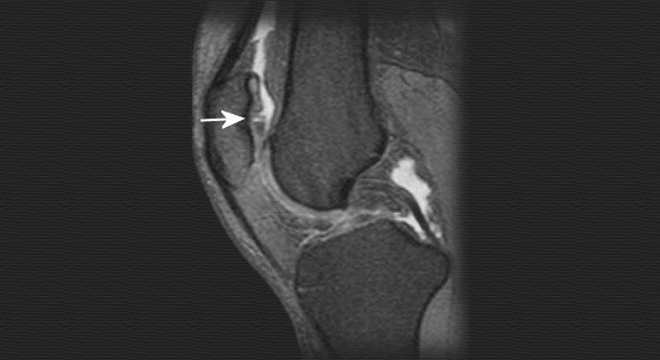

• Magnetresonanztomographie (MRT): Beurteilung des Kniegelenkknorpels, eines allfälligen Knorpelschadens sowie der Weichteile des Kniegelenks